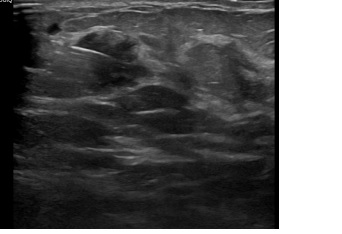

상기환자는 외부건진이상소견 조직검사위해 내원하신 70대 후반

여성분으로 의심스러운 좌측혹 조직검사 시행해 유방암 진단되었습니다.